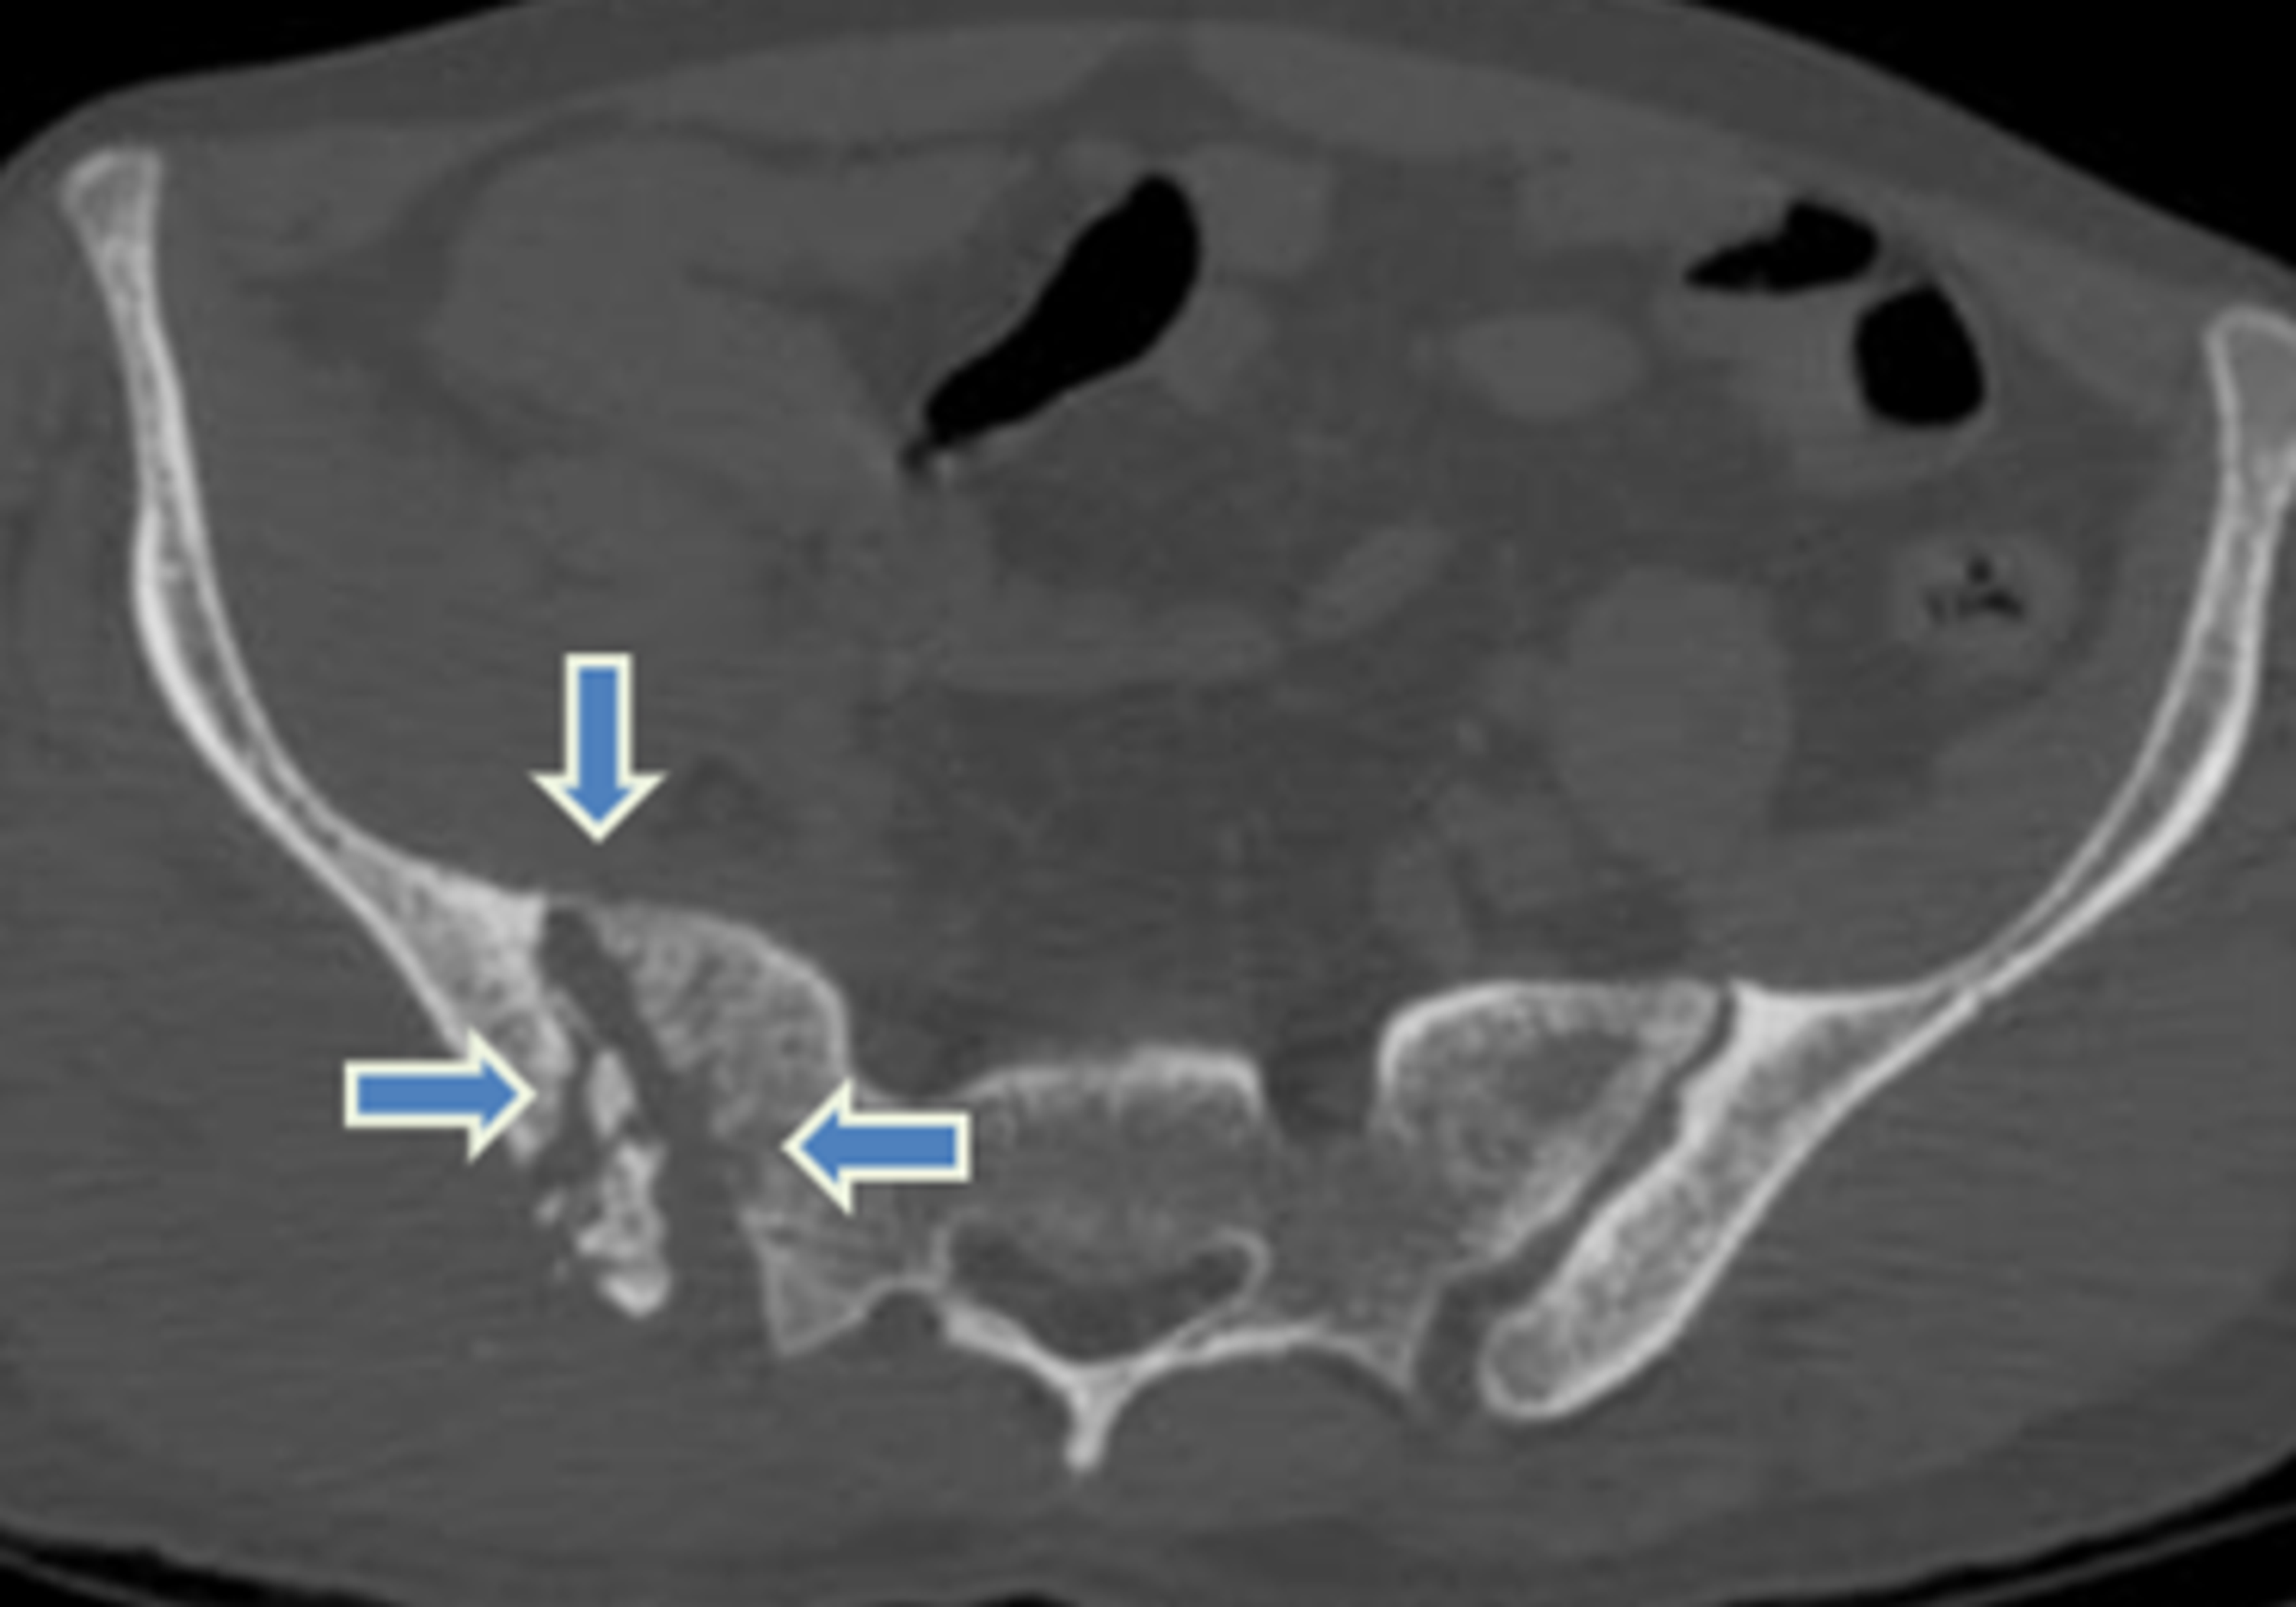

Iliac Bone Anatomy Axial. Atlas of CT Anatomy of the Abdomen. How to view anatomical labels.